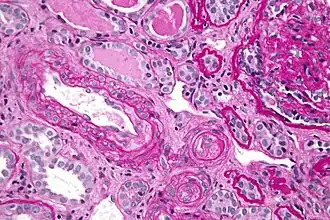

Micrograph showing thrombotic microangiopathy, the histomorphologic finding seen in scleroderma renal crisis, kidney biopsy, PAS stain

Kidney involvement, in scleroderma, is considered a poor prognostic factor and frequently a cause of death.[14]

The most important clinical complication of scleroderma involving the kidney is scleroderma renal crisis (SRC), the symptoms of which are malignant hypertension (high blood pressure with evidence of acute organ damage), hyperreninemia (high renin levels), azotemia (kidney failure with accumulation of waste products in the blood), and microangiopathic hemolytic anemia (destruction of red blood cells).[15] Apart from the high blood pressure, hematuria (blood in the urine) and proteinuria (protein loss in the urine) may be indicative of SRC.[16]

In the past, SRC was almost uniformly fatal.[17] While outcomes have improved significantly with the use of ACE inhibitors,[18][19] the prognosis is often guarded, as a significant number of patients are refractory to treatment and develop kidney failure. About 7–9% of all diffuse cutaneous scleroderma patients develop renal crisis at some point in the course of their disease.[20][21] Patients who have rapid skin involvement have the highest risk of renal complications.[22] It is most common in diffuse cutaneous scleroderma, and is often associated with antibodies against RNA polymerase (in 59% of cases). Many proceed to dialysis, although this can be stopped within three years in about a third of cases. Higher age and (paradoxically) a lower blood pressure at presentation make dialysis more likely to be needed.[23]